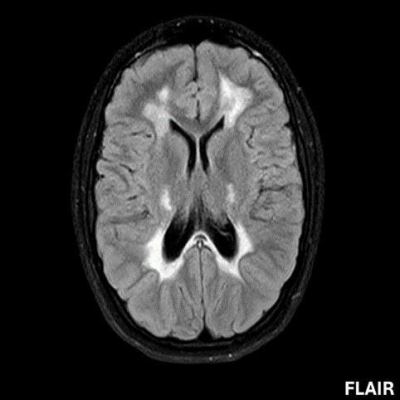

- A) Aksiyel T2A ve koronal T2A sekanslarda sentrum semiovale, korona radiata ve bazal ganglionlar düzeyinde bilateral frontoparietal derin periventriküler beyaz cevherde birleşme eğilimi gösteren hiperintens gliotik sinyal değişiklikleri (oklar) ve aksiyel T2A serilerde servikal spinal kordda posterior kolonda, lateral kesimlerde sinyal artımları (oklar) izlendi.

- LBSL, karakteristik radyolojik özelliklere sahiptir. MRG’de tipik olarak bilateral ve simetrik beyaz cevher sinyal değişiklikleri görülürken, subkortikal U lifleri, internal kapsülün posterior kolları, trigeminal sinir traktları, serebellum, korpus kallozumun spleniumu, medulla oblongata ve omurilikteki dorsal kolonlar ile lateral kortikospinal traktlar genellikle korunur.

- Etkilenen bölgelerde T1’de hipointens, T2/FLAIR’da hiperintens sinyal değişiklikleri izlenir. DWI’de lezyonların periferinde kısıtlı difüzyon görülebilir. MRS’de beyaz cevherde laktat artışı saptanabilir, ancak bu her hastada mevcut değildir.